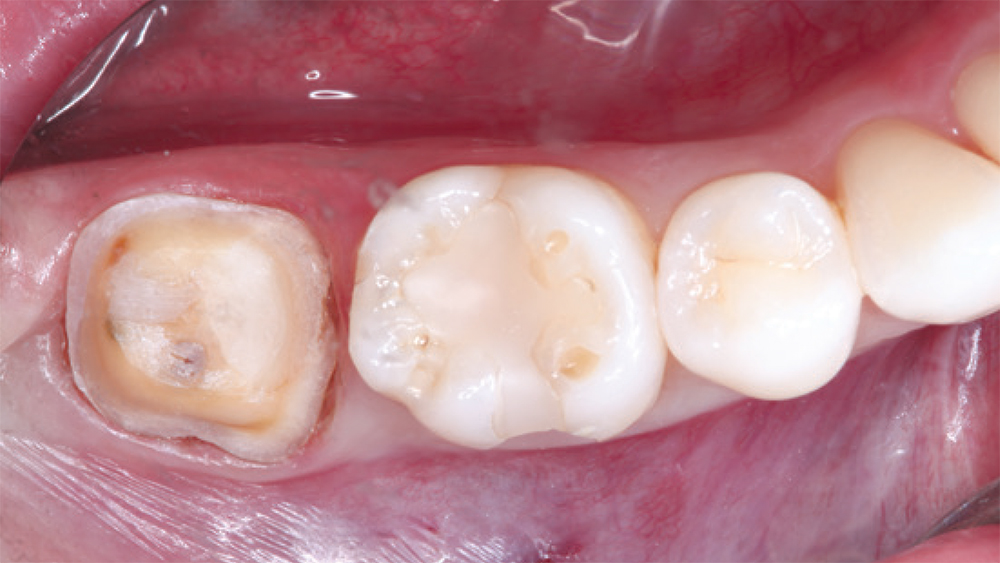

fracture premolar

CAMouflage NOW restoration

This fractured premolar was replaced by a CAMouflage NOW restoration that was designed and milled in-office in less than 10 minutes, addressing the patient’s urgent dental situation in a single appointment.